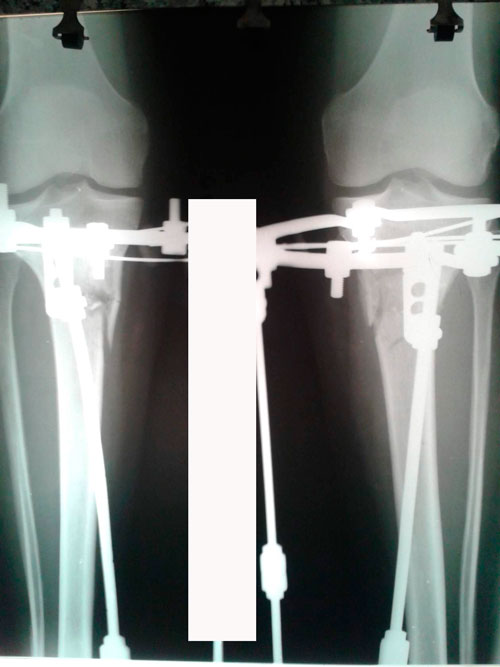

рентген в 20 дней после операции.